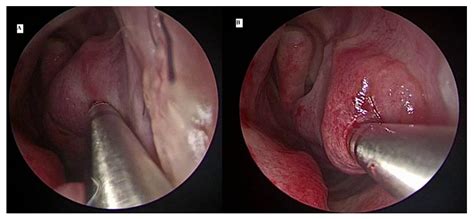

- Nasal Endoscopy: A thin, flexible tube with a camera (endoscope) is inserted into the nasal cavity, allowing the doctor to see the exact size and state of your turbinates in real-time.

| Color | Light pink, moist | Deep red, purple, or pale/boggy |

| Size | Slim, allowing clear airway | Bulky, filling the nasal cavity |

| Mucosa | Smooth and thin | Swollen, edematous, or textured |

| Airflow | Clear and unobstructed | Severely restricted or blocked |